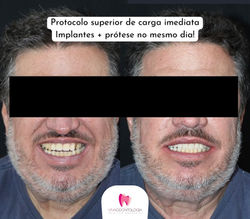

diastema.jfif |  Untitled |  Protocolo superior de carga imediata Implantes +prótese no mesmo dia! |